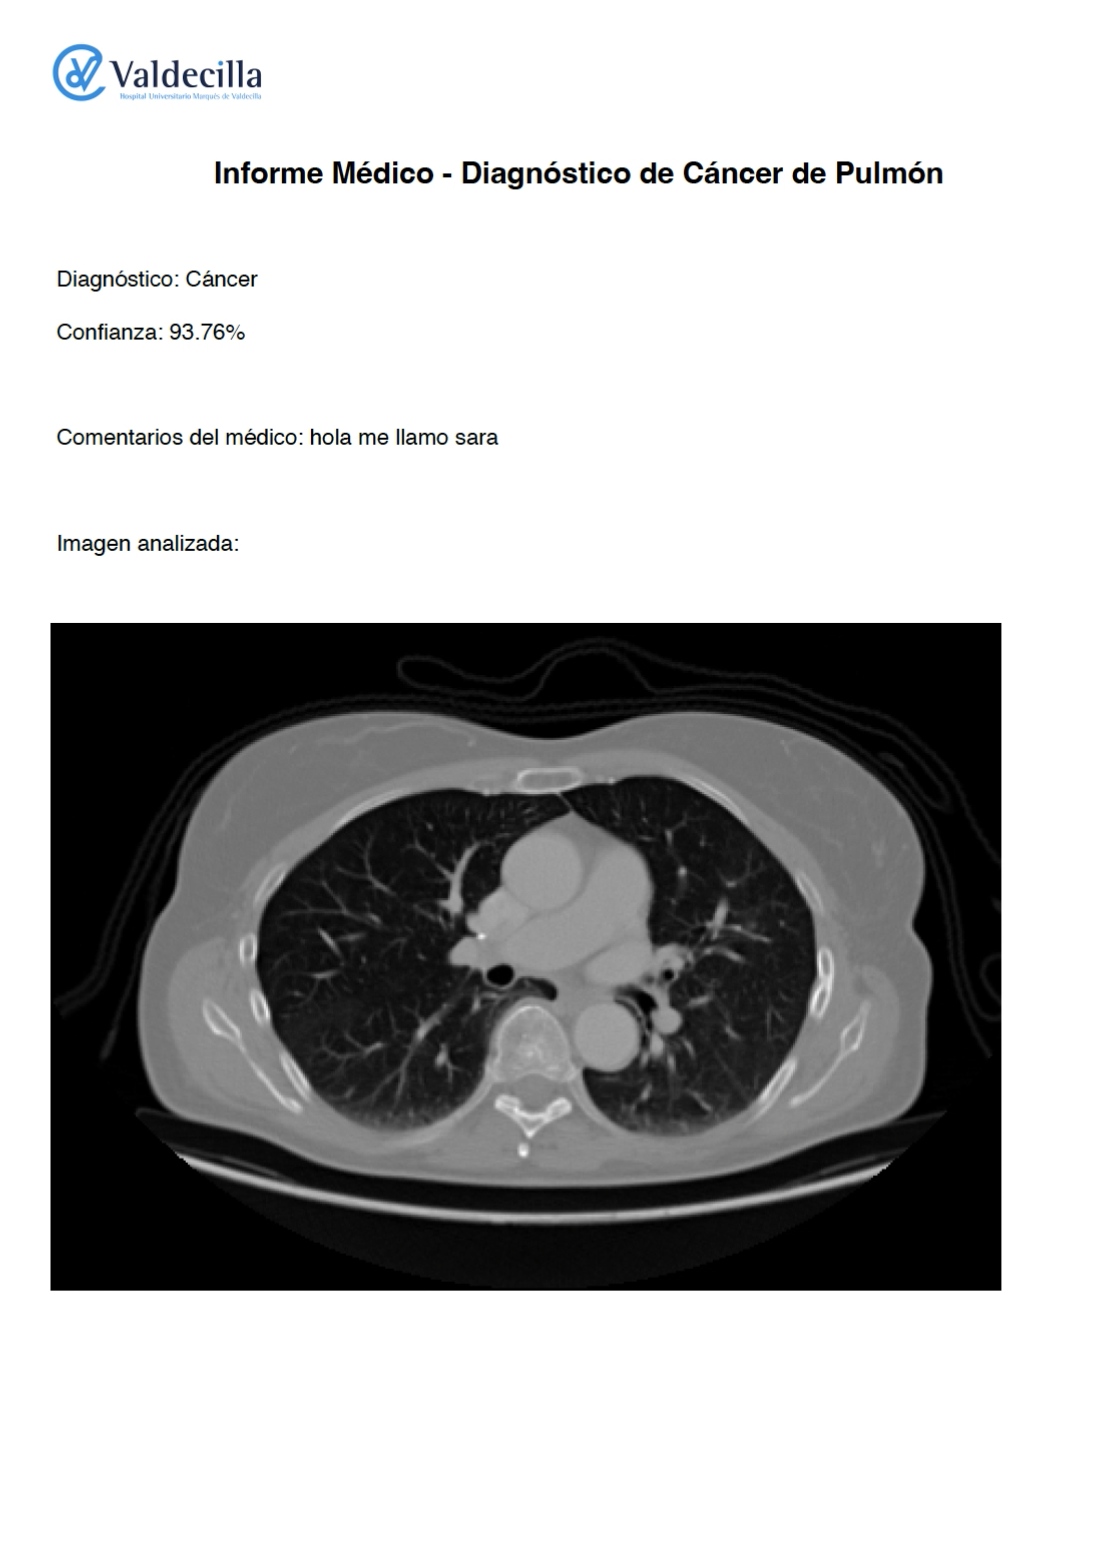

Below is a demonstration of the LungAI project: